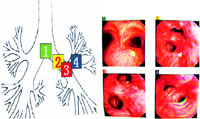

3支气管镜检查 原因不明的咯血或支气管阻塞肺不张的患者应考虑支气管镜检查,如肿瘤、结核异物等,同时在直视同上取活体组织病理检查或异物取出,出血和痰液吸出等

支气管镜检查直视下可见支气管结核病灶,刷检涂片和冲洗沉淀法涂片查结核菌和瘤细胞或咬检进行组织学检查可明确诊断。